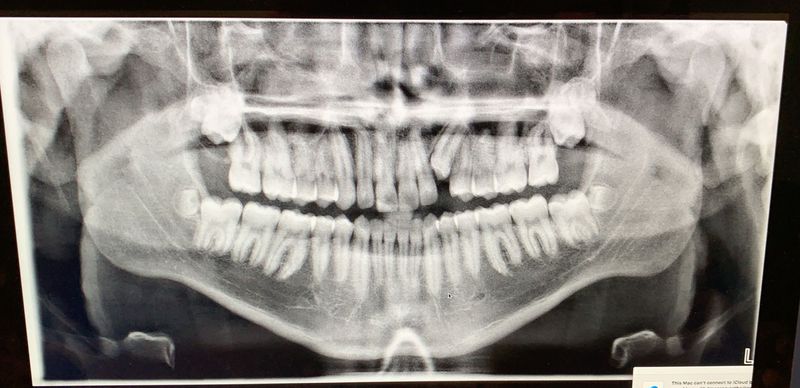

8 Wisdom teeth

Aside from the impacted k9, look around. Count how many teeth you see. All the wisdoms are there but oh wait....

Wow! That's a mouthful!!πŸ˜‚